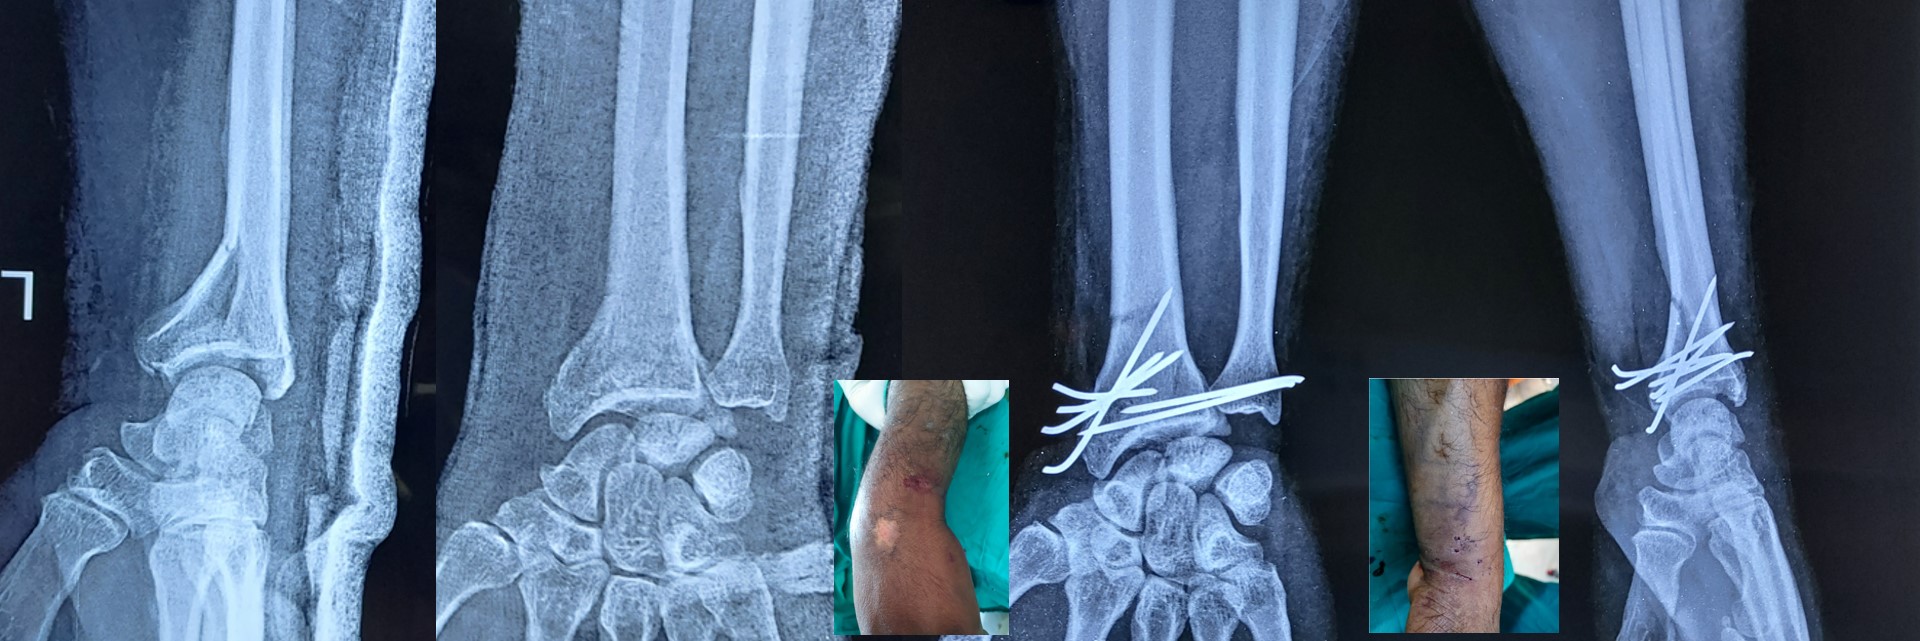

CRPP ( Closed Reduction Percutaneous Pinning )

• It can be applied to any intraarticular fractures, distal end radius, elbow, ankle and foot.

• It can be applied safely in fractures, where ORIF (Open Reduction Internal Fixation ) cannot be performed or postponed due to impending soft tissue complications.

• Almost all complications of open surgeries can be avoided by CRPP with very minimal complications.